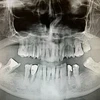

Diş Çürükleri

Diş Eksikliği

Diş ve Diş eti hastalıkları

Periimplantitis